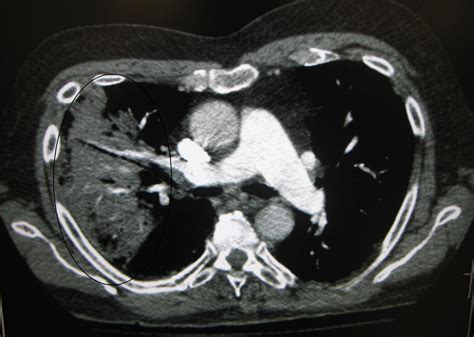

Once the scan is completed, a radiologist will interpret the images and generate a report. When viewing a Pneumonia CT Scan, medical professionals look for specific patterns of lung involvement. These patterns often indicate the type of pneumonia or the severity of the inflammatory response.

Common findings often described in reports include:

• Consolidation: This refers to the filling of air spaces (alveoli) with fluid, pus, or other material, appearing as dense, white areas on the scan.

• Ground-Glass Opacity (GGO): A hazy appearance in the lungs, indicating partial filling of air spaces or thickening of the lung interstitium. This is often seen in viral pneumonias.

• Bronchograms: The appearance of air-filled bronchi surrounded by consolidated lung tissue.

• Pleural Effusion: The buildup of fluid in the space between the lung and the chest wall.

• Nodules or Cavitation: These findings may prompt further investigation to rule out other infections or malignancy.

It is important to remember that these findings must always be correlated with the patient's symptoms, laboratory results, and clinical history. A report with "positive findings" does not always imply a worst-case scenario, as many patterns are typical of common bacterial or viral infections.